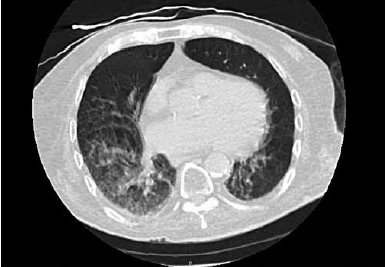

Paciente de 90 anos e admitido no pronto-socorro com história de 1 dia de evolução de tosse, sonolência e diminuição da ingestão de alimentos. Foi realizada uma tomografia computadorizada de tórax, apresentada a seguir:

(Arquivo pessoal; imagem usada com autorização)

Em relação ao caso, assinale a alternativa correta.